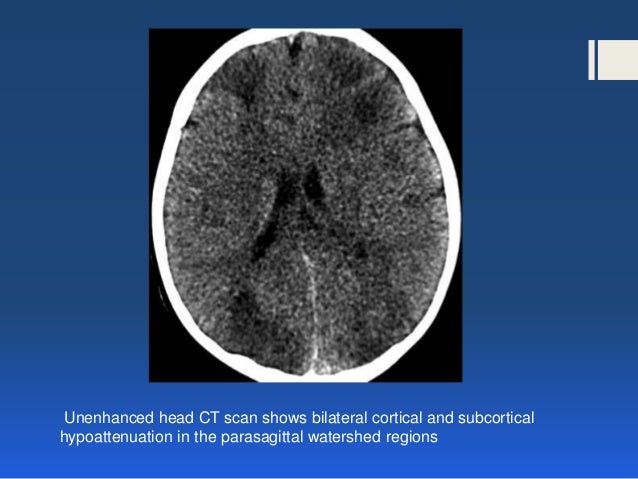

An anoxic brain injury occurs when the brain is starved of oxygen. Hypoxic/anoxic brain injuries can occur due to one or more of the following issues treatment for hypoxic/anoxic brain injury. In adults, typically occurs after cardiac arrest, trauma or.

Related online courses on physioplus. Anoxic injuries are often devastating because the brain uses oxygen to convert glucose into energy. Any event that prohibits you from breathing could potentially result in an anoxic brain. Degree of injury proportional to duration and severity of oxygen overview.